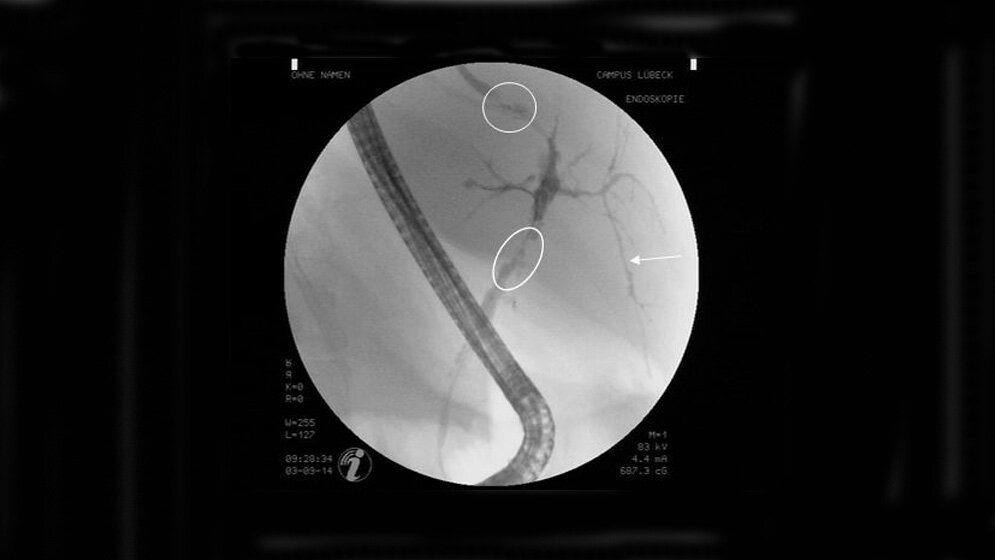

Das Gallengangkarzinom ist in Frühstadien, in denen eine Heilung durch Operation noch möglich wäre, extrem schwierig zu diagnostizieren. Autoantikörper gegen GP2 könnten dabei helfen, PSC-Patienten mit besonders hohem Krebsrisiko zu identifizieren. „Insbesondere muss nun geklärt werden, ob entsprechende Patienten von einer intensivierten Früherkennungsdiagnostik oder auch einer frühen Lebertransplantation profitieren“, so das Fazit von Prof. Christian Sina, dem Leiter der Studie.

In seiner Arbeit beschreibt Dr. Jendrek erstmalig einen engen Zusammenhang zwischen dem Auftreten von Autoantikörpern der Bauchspeicheldrüse (Pankreas) und dem Krankheitsbild der Gallengangsentzündung (primäre sklerosierende Cholangitis, PSC) sowie des mit PSC verbundenen Gallengangkarzinoms. Neben dem Lübecker Team, zu dem unter anderem Dr. Stefanie Derer und Prof. Marc Ehlers aus dem in Gründung befindlichen Lübecker Institut für Ernährungsmedizin gehören, waren auch Forscher der Universitäten Heidelberg und Oslo sowie Mitarbeiter der Firma Euroimmun beteiligt.

PSC gehört zu den mit einer Gallestauung verbundenen (cholestatischen) Lebererkrankungen. Sie tritt vor allem im Zusammenhang mit chronisch entzündlichen Darmerkrankungen auf. Pathophysiologisch liegt eine chronische, vermutlich bakteriell und autoimmun getriebene Entzündung der Gallenwege vor, die über den Verlauf der Erkrankung zu einer Verengung der Gallengänge und damit zur Abflussbehinderung der Galle führt. Hierdurch werden Gallenweginfektionen mit septischen Komplikationen sowie Gallenwegtumore begünstigt. Die Ursachen für PSC sind weitgehend unbekannt. Die Lebertransplantation stellt die einzige Behandlungsoption für die Betroffenen dar, die zu einer vollständigen Heilung führt. (idw, red)